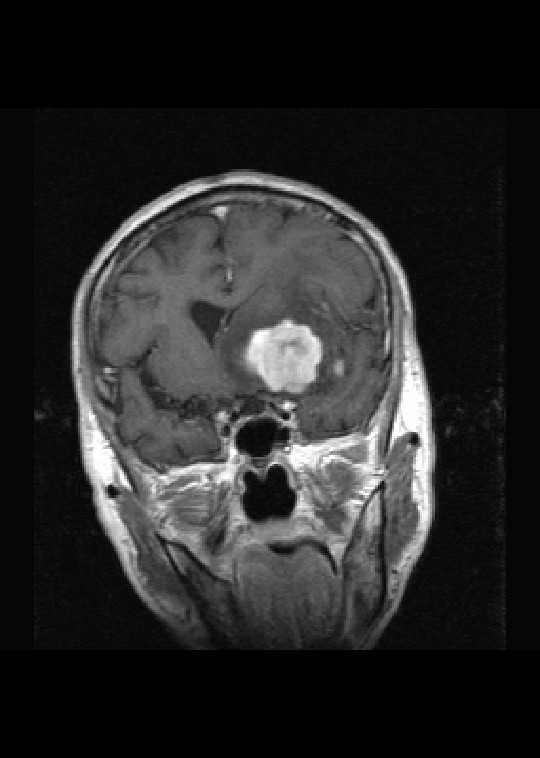

标题: MRI2527:脑部肿瘤,(病理结果:淋巴瘤)

(左额颞叶)非霍奇金淋巴瘤,b细胞性,弥漫性大b细胞型。免疫组化结果:cd45(lca) +,vimentin +,ck(ae1/ae3) -,ema -,cd3 -,cd20 +++,cd30 -,plap -,cd79a +,gfap -,alk -,s-100 -。

左侧基底节区病灶t1wi呈不均匀稍低信号,t2wi呈稍高信号,周围伴有水肿。增强扫描呈均匀团块样或者抱拳样明显强化,相邻的柔脑膜亦见线样强化。首先考虑淋巴瘤。可惜没有ct平扫,如果ct平扫病灶呈高密度,那么更支持pcnsl的诊断。

病理结果:(左额颞叶)非霍奇金淋巴瘤,b细胞性,弥漫性大b细胞型。免疫组化结果:cd45(lca) +,vimentin +,ck(ae1/ae3) -,ema -,cd3 -,cd20 +++,cd30 -,plap -,cd79a +,gfap -,alk -,s-100 -。

淋巴瘤可能性大,考虑侵犯侧脑室

左侧基底节区病灶t1wi呈不均匀稍低信号,t2wi呈稍高信号,周围伴有水肿。增强扫描呈均匀团块样或者抱拳样明显强化,首先考虑淋巴瘤。

淋巴瘤,信号及强化方式较典型。灶周方广泛水肿相对较少见。长见识了。